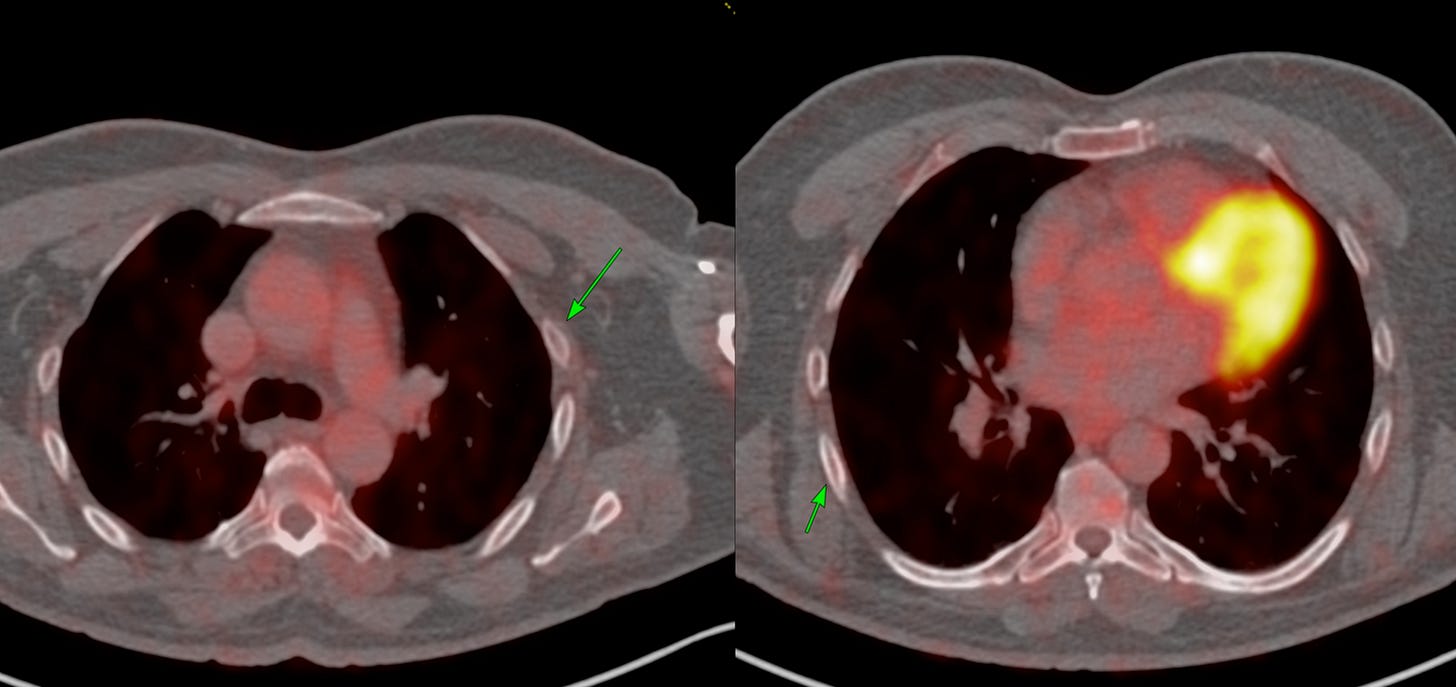

A repeat FDG PET done 2 weeks later shows no uptake in those areas and no morphologic rib lesion (Fig. 2).

This is a known pitfall with PSMA PET for some reason. Isolated benign rib uptake without disease.